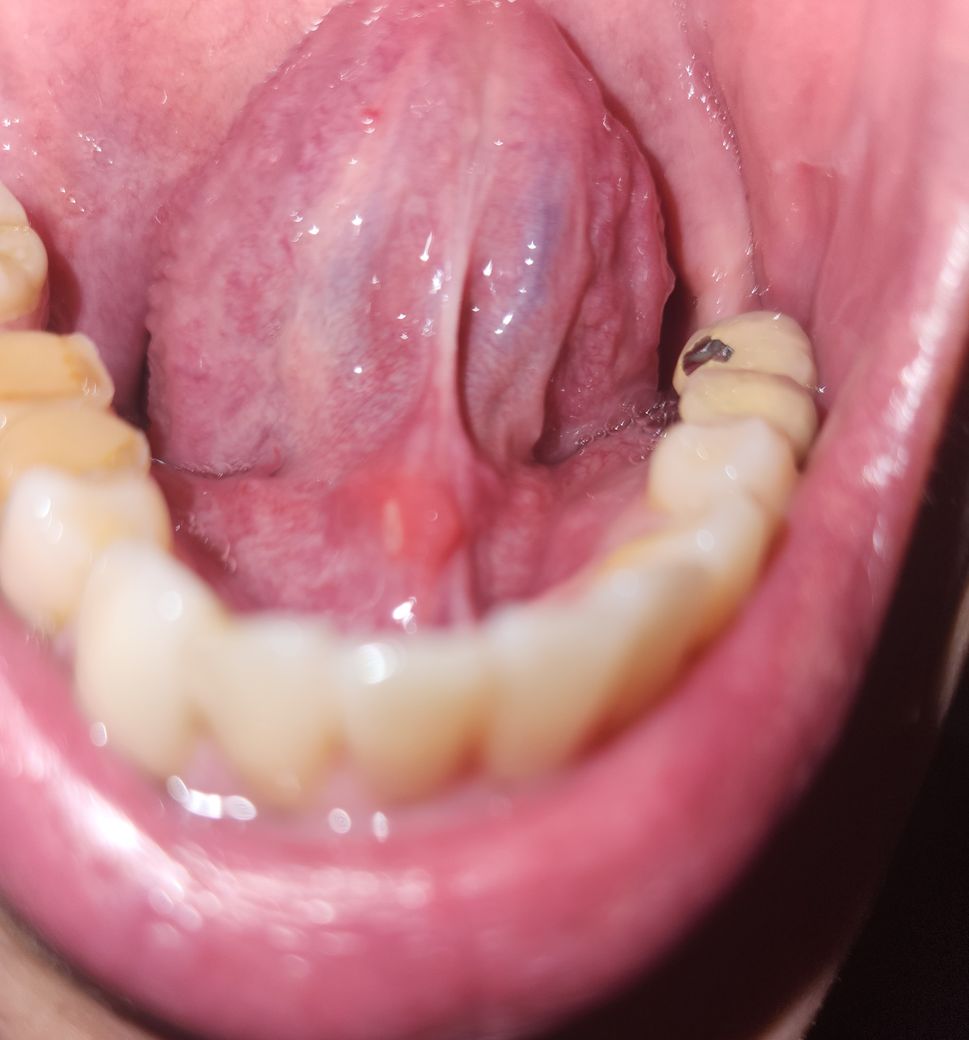

혀밑에 혹이 생겼는데 무슨 질환일까요~?

혀밑이 따갑길래 구내염이 생겼나 했습니다.

근데 혀밑을보니 혀밑에 혹과 구내염이 생겼는데 무슨 질환일까요~?

큰병일수도 있는지 여쭈어봅니다

• 1번 째 사진